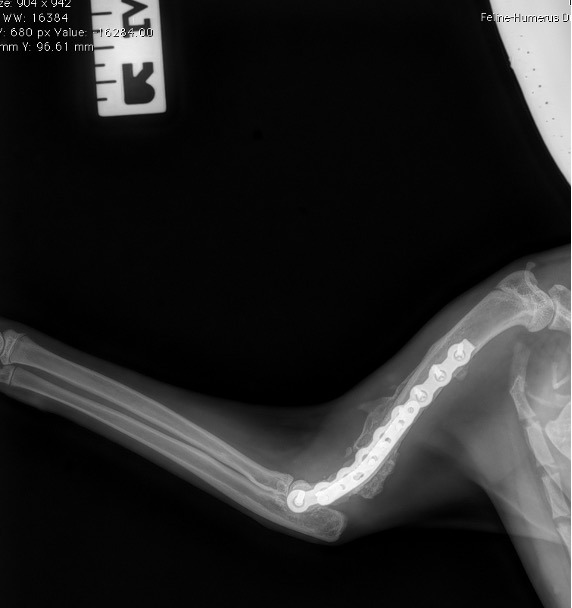

Exemple 2 :

Figure 4 : Pré-Op

Figure 5 : Post-Op Immédiat

Figure 6 : Post-Op 1 mois

Figure 7 : Post-Op 2 mois